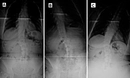

Fizik Tedavi ve Egzersiz: Fizik tedavi, skolyozun ilerlemesini durdurmak ve postürü düzeltmek için önemli bir rol oynar. Hastalara özel egzersiz programları uygulanır. Bu programlar, kas gücünü artırmayı ve esnekliği geliştirmeyi hedefler. Ortez Kullanımı: Ortezler, omurganın düzeltilmesine yardımcı olmak için kullanılan cihazlardır. Özellikle büyüme çağındaki çocuklar için etkili olabilir. Ortezlerin kullanım süresi, skolyozun şiddetine bağlı olarak değişir. Cerrahi Müdahale: Eğer skolyoz ilerliyorsa ve diğer tedavi yöntemleri yeterli olmuyorsa cerrahi müdahale gerekebilir. Cerrahi işlemler genellikle omurganın düzeltilmesi ve stabilizasyonunu hedefler. Bu tür bir müdahale, hastanın yaşına, genel sağlık durumuna ve skolyozun şiddetine göre planlanır. SonuçSkolyoz tedavisi, bireysel ihtiyaçlara göre özelleştirilmelidir. Tedavi yöntemleri arasında fizik tedavi, ortez kullanımı ve cerrahi müdahale gibi seçenekler bulunmaktadır. Erken tanı ve uygun tedavi, skolyozun yönetiminde kritik öneme sahiptir. Her birey için en uygun tedavi yönteminin belirlenmesi, uzman bir hekim tarafından yapılmalıdır. Ek BilgilerSkolyoz hastalarının takip edilmesi ve düzenli kontrollerin yapılması, tedavi sürecinin etkinliği açısından önemlidir. Ayrıca, skolyozun psikolojik etkileri de göz önünde bulundurulmalıdır. Hastaların duygusal destek alması, tedavi sürecini olumlu yönde etkileyebilir. Skolyoz ile ilgili daha fazla bilgi ve destek almak için uzman sağlık profesyonellerine başvurulması önerilmektedir. |